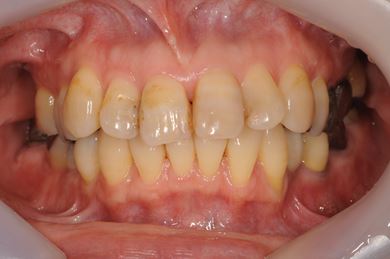

| 性別/年齢 | 女性 / 54歳 | ||||||||||||||||||||||||||||||||

| 主訴 | 下顎の奥歯を抜歯したままになっており、歯茎が少しやせて、両側の歯が少し倒れているような気がする。可能であればインプラントを入れたい。 | ||||||||||||||||||||||||||||||||

| 治療内容 | インプラント1本、メタルボンドセラミック1本 | ||||||||||||||||||||||||||||||||